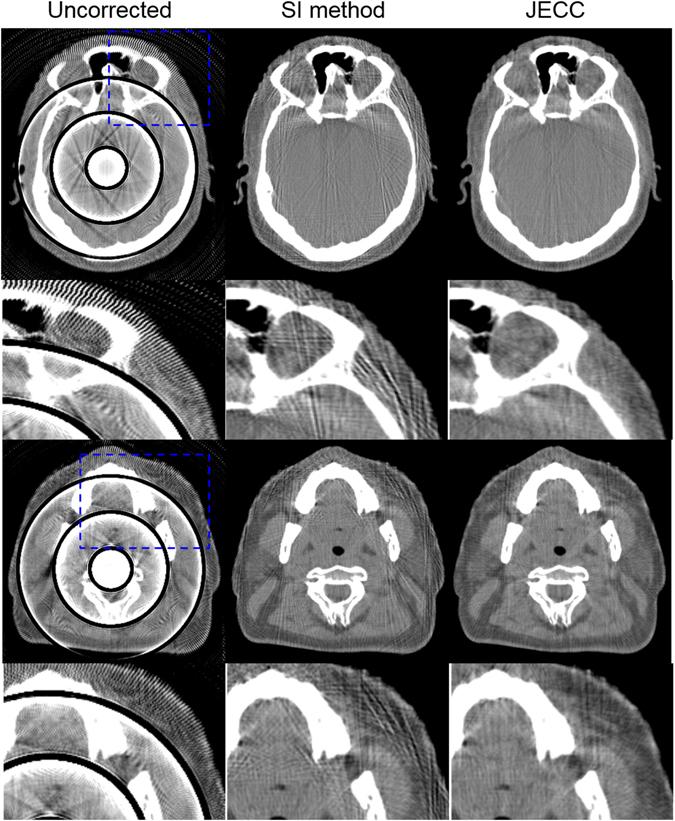

In transmitted X-ray tomography imaging, the acquired projections may be corrupted for various reasons, such as defective detector cells and beam-stop array scatter correction problems. In this study, we derive a consistency condition for cone-beam projections and propose a method to restore lost data in corrupted projections. In particular, the relationship of the geometry parameters in circular trajectory cone-beam computed tomography (CBCT) is utilized to convert an ultra-hyperbolic partial differential equation (PDE) into a second-order PDE. The second-order PDE is then transformed into a first-order ordinary differential equation in the frequency domain. The left side of the equation for the newly derived consistency condition is the projection derivative of the current and adjacent views, whereas the right side is the projection derivative of the geometry parameters. A projection restoration method is established based on the newly derived equation to restore corrupted data in projections in circular trajectory CBCT. The proposed method is tested in beam-stop array scatter correction, metal artifact reduction, and abnormal pixel correction cases to evaluate the performance of the consistency condition and corrupted projection restoration method. Qualitative and quantitative results demonstrate that the present method has considerable potential in restoring lost data in corrupted projections.

在透射 X 射线断层成像中,由于探测器单元损坏和射束挡块阵列散射校正问题等各种原因,采集的投影可能会受到损坏。在本研究中,我们推导出了锥束投影的一致性条件,并提出了一种在损坏的投影中恢复丢失数据的方法。具体来说,我们利用圆轨迹锥束计算机断层扫描(CBCT)中的几何参数关系,将超双曲型偏微分方程(PDE)转换为二阶 PDE。然后,二阶 PDE 在频域中转换为一阶常微分方程。新推导的一致性条件方程的左侧是当前和相邻视图的投影导数,而右侧是几何参数的投影导数。基于新推导的方程,建立了一种投影恢复方法,用于恢复圆轨迹 CBCT 中投影中的损坏数据。该方法在射束挡块阵列散射校正、金属伪影减少和异常像素校正情况下进行了测试,以评估一致性条件和损坏投影恢复方法的性能。定性和定量结果表明,该方法在恢复损坏投影中的丢失数据方面具有很大的潜力。